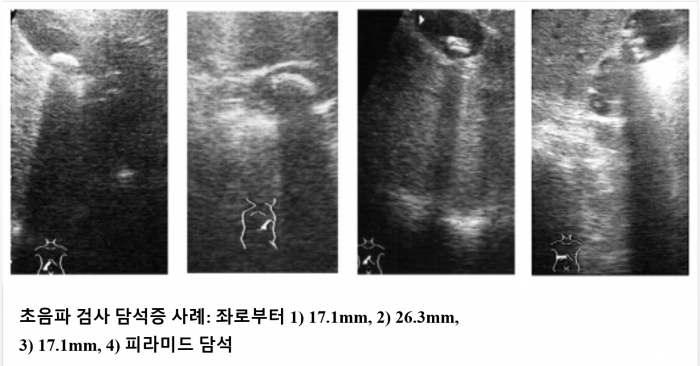

일단 우리 몸에 일어날 수 있는 여러 가지 증상들은 사실 특발성인 경우도 있지만 뚜렷한 원인이 존재하는 경우도 있습니다. 특히 오른쪽 옆구리의 통증은 담석증과 상당한 관계를 가지고 있는 증상임을 명심해야 하는데 이 질환은 콜레스테롤이 굳어 돌처럼 형성되면서 담관 입구를 막을 경우 염증이 생겨서 나타나는 질환이라고 보시면 되겠습니다. 즉, 담낭에 돌이 생겨 막히거나 염증을 일으켜 버린 질환이라는 것이군요. 사실 하나만 발생하는 게 아니라 꺼내다 보면 수십 개까지도 발견되는 사례가 있는데 크기도 생각보다 다양할 수 있어 주의가 필요합니다. 또 초기에는 오른쪽 옆구리의 통증 자체가 심하다기보다는 아픈 정도만 발생하는 사례가 많지만 점차 염증이 심해질 경우 출산과 비슷한 것으로 알려진 심한 복통이 발생할 수도 있습니다. 그래서 숨을 쉴 수 없을 정도의 통증이 있는 것이라면 이미 병기가 어느 정도 진행된 상태라고 봐도 좋을 것입니다. 일단 우리 몸에 일어날 수 있는 여러 가지 증상들은 사실 특발성인 경우도 있지만 뚜렷한 원인이 존재하는 경우도 있습니다. 특히 오른쪽 옆구리의 통증은 담석증과 상당한 관계를 가지고 있는 증상임을 명심해야 하는데 이 질환은 콜레스테롤이 굳어 돌처럼 형성되면서 담관 입구를 막을 경우 염증이 생겨서 나타나는 질환이라고 보시면 되겠습니다. 즉, 담낭에 돌이 생겨 막히거나 염증을 일으켜 버린 질환이라는 것이군요. 사실 하나만 발생하는 게 아니라 꺼내다 보면 수십 개까지도 발견되는 사례가 있는데 크기도 생각보다 다양할 수 있어 주의가 필요합니다. 또 초기에는 오른쪽 옆구리의 통증 자체가 심하다기보다는 아픈 정도만 발생하는 사례가 많지만 점차 염증이 심해질 경우 출산과 비슷한 것으로 알려진 심한 복통이 발생할 수도 있습니다. 그래서 숨을 쉴 수 없을 정도의 통증이 있는 것이라면 이미 병기가 어느 정도 진행된 상태라고 봐도 좋을 것입니다.